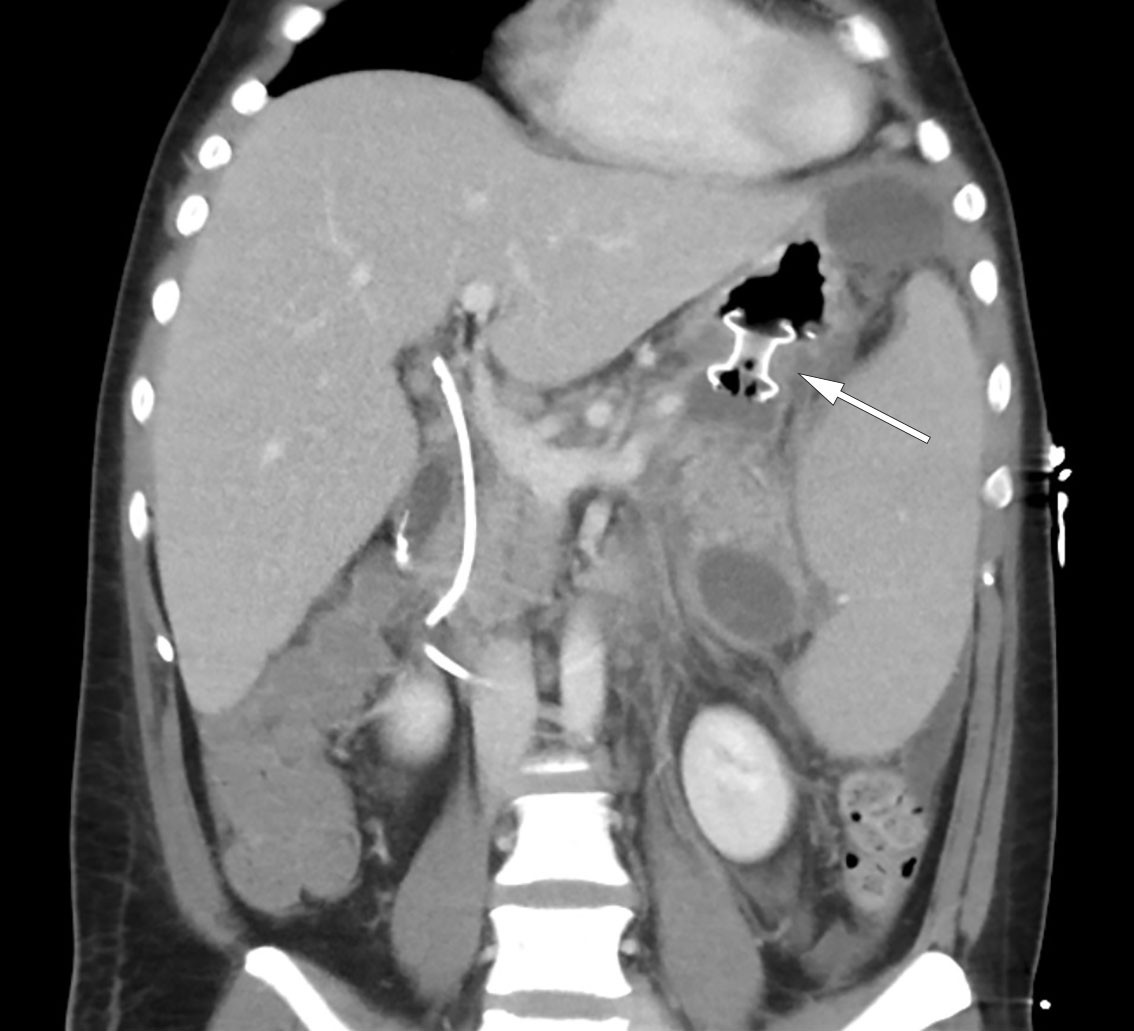

Over the course of day 3, the patient's clinical condition deteriorated further and he developed severe abdominal pain. He was transferred to the intensive care unit due to incipient organ failure with a need for oxygen. He was somnolent and, although breathing independently, required 2–3 L of O2 via nasal catheter to maintain oxygen saturation above 92 %. His INR level had increased to 1.9 while his albumin level had fallen to 22 g/L (from 45.6 g/L), raising suspicion of a bleeding disorder. In addition, his bilirubin level had increased once again to 290 μmol/L, but in the absence of any other liver or bile enzyme increases, it was decided based on an interdisciplinary discussion not to proceed immediately with another ERC examination. Further diagnostic imaging with a CT scan of the abdomen and pelvis revealed necrotising pancreatitis with peripancreatic fluid collections and free fluid in the abdomen (Figure 2). There were no signs of intra- or extrahepatic cholestasis. However, bilateral pleural effusion and atelectasis were observed, which could explain the deterioration in respiratory function. Due to the patient's elevated INR level, a pleural tap was not performed. Enlargement of the spleen (21 cm in length) was also noted.